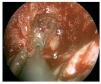

Caso clínico: Varón de 42 años de edad con paresia del VI par craneal derecho y estudios de imagen mediante resonancia magnética y tomografía computarizada craneales sugestivos de displasia fibrosa esfenoclival. Se lleva a cabo un abordaje endonasal expandido transpterigoideo completamente endoscópico, obteniéndose una amplia descompresión de las estructuras vasculonerviosas de la base del cráneo. Durante el procedimiento se utiliza neuronavegación y el canal vidiano como referencia anatómica fundamental de la carótida en su segmento lacerum.

Case report: A 42-year-old male with right sixth cranial nerve palsy. Cranial MRI and CT showed a central skull base lesion with diagnostic suspicion of FD. Patient underwent a full endoscopic transpterygoid EEA, achieving a wide skull base neurovascular decompression. Neuronavigation and the vidian canal landmark resulted mandatory during intraoperative procedure.

Discusión: El AEE transterigoideo es una técnica segura y con amplio sustento en la literatura científica. En manos adecuadas, podría reducir la morbilidad asociada a los abordajes transcraneales clásicos, ya que permite un máximo potencial resectivo sobre las lesiones a tratar, con una mínima distorsión sobre las estructuras craneofaciales circundantes. Para su realización se utilizan referencias anatómicas claves como el agujero y canal del nervio vidiano. La indicación de tratamiento quirúrgico en los casos de DF de base craneal ha de establecerse en función de la presencia de sintomatología.

Discussion: The transpterygoid EEA is a safe technique consistently supported in the literature. It may reduce the morbidity associated to the classic transcranial approaches, since it permits maximum resection with minimum craniofacial distortion. The vidian hole and canal are the landmarks used to locate and avoid injury to the lacerum segment of the carotid injury. The surgical treatment indication in FD cases must be established in symptomatic patients.